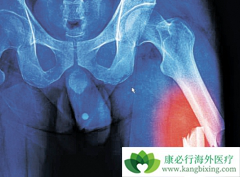

在骨髓瘤的发病患者当中,大多是中年和晚年患者,这个疾病大多发于年龄段在40-60岁。而且我们平时说的骨髓瘤,多属于多发性骨髓瘤,它的发病率是比较高的。恶性骨髓瘤在人的椎体,肋骨,胸骨,颅骨和骨盆为其好发部位。早期 骨髓瘤能治好吗 ? 早期 ...